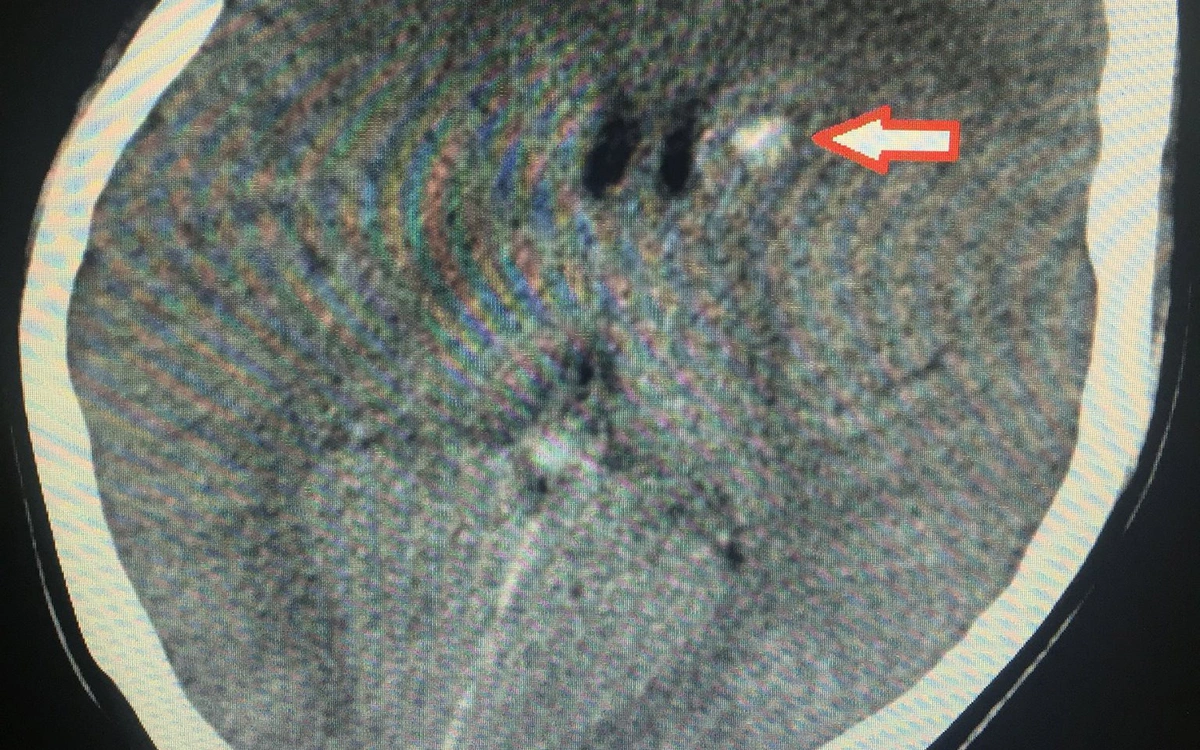

Cô gái trẻ đến viện trong tình trạng vùng đùi trái sưng nề, nóng, đỏ, đau dữ dội, khối tổn thương có đường kính lên tới khoảng 10cm.